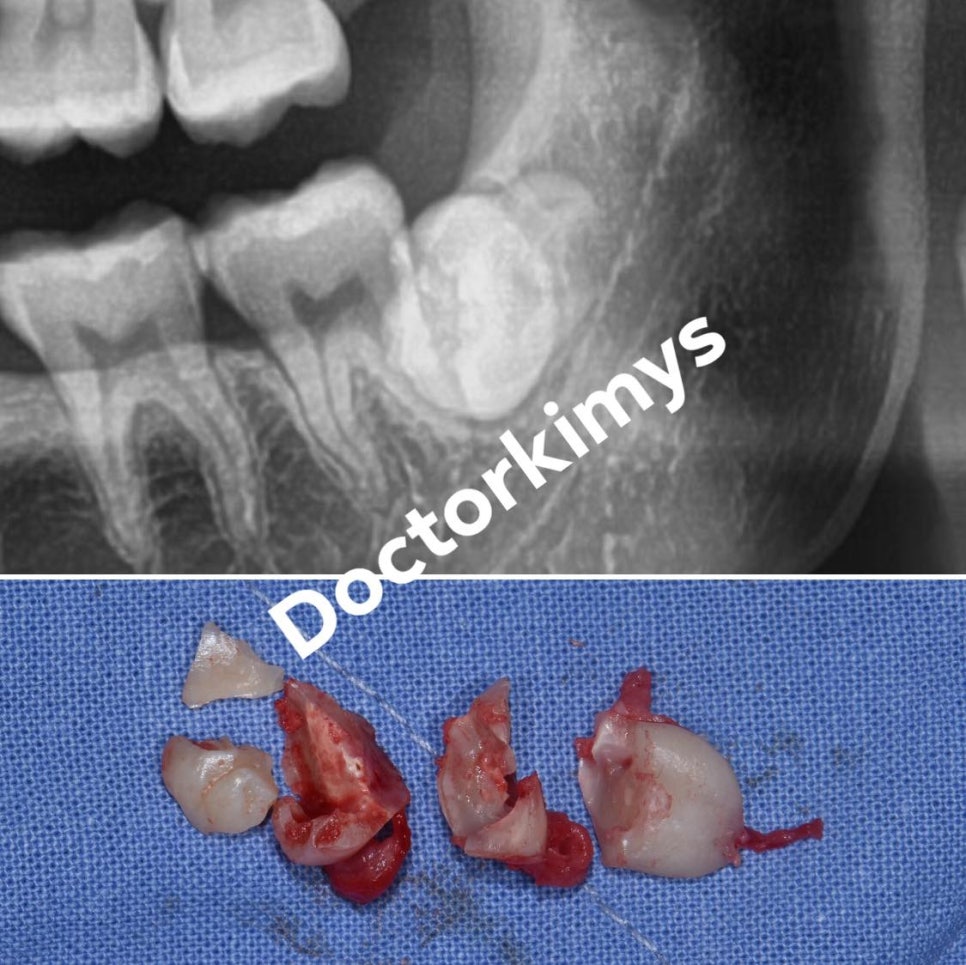

저희 원장님의 케이스를 보여드려볼께요.

기울어져 있거나 매복 된 제3대구치를 뽑을 땐 많은 분들이

치아도 쪼개고, 뼈도 깎아낸다는 생각을 많이 하십니다.

이 사례는 저희 원장님께서 치조골 삭제 없이 오로지 치아만 쪼개어 발거를 한 경우랍니다.

이렇게 뽑고 나면 왠만한 분들은 통증과 붓기가 없어

다음날 소독을 하러 오실 때 굉장히 편안해 하는 모습을 볼 수 있어요.

당장 이를 뽑는 것만 열심히 하는 것이 아니라

다음날 붓기와 통증까지 고려하니까 사랑니 발치 전문 맞죠!?^^